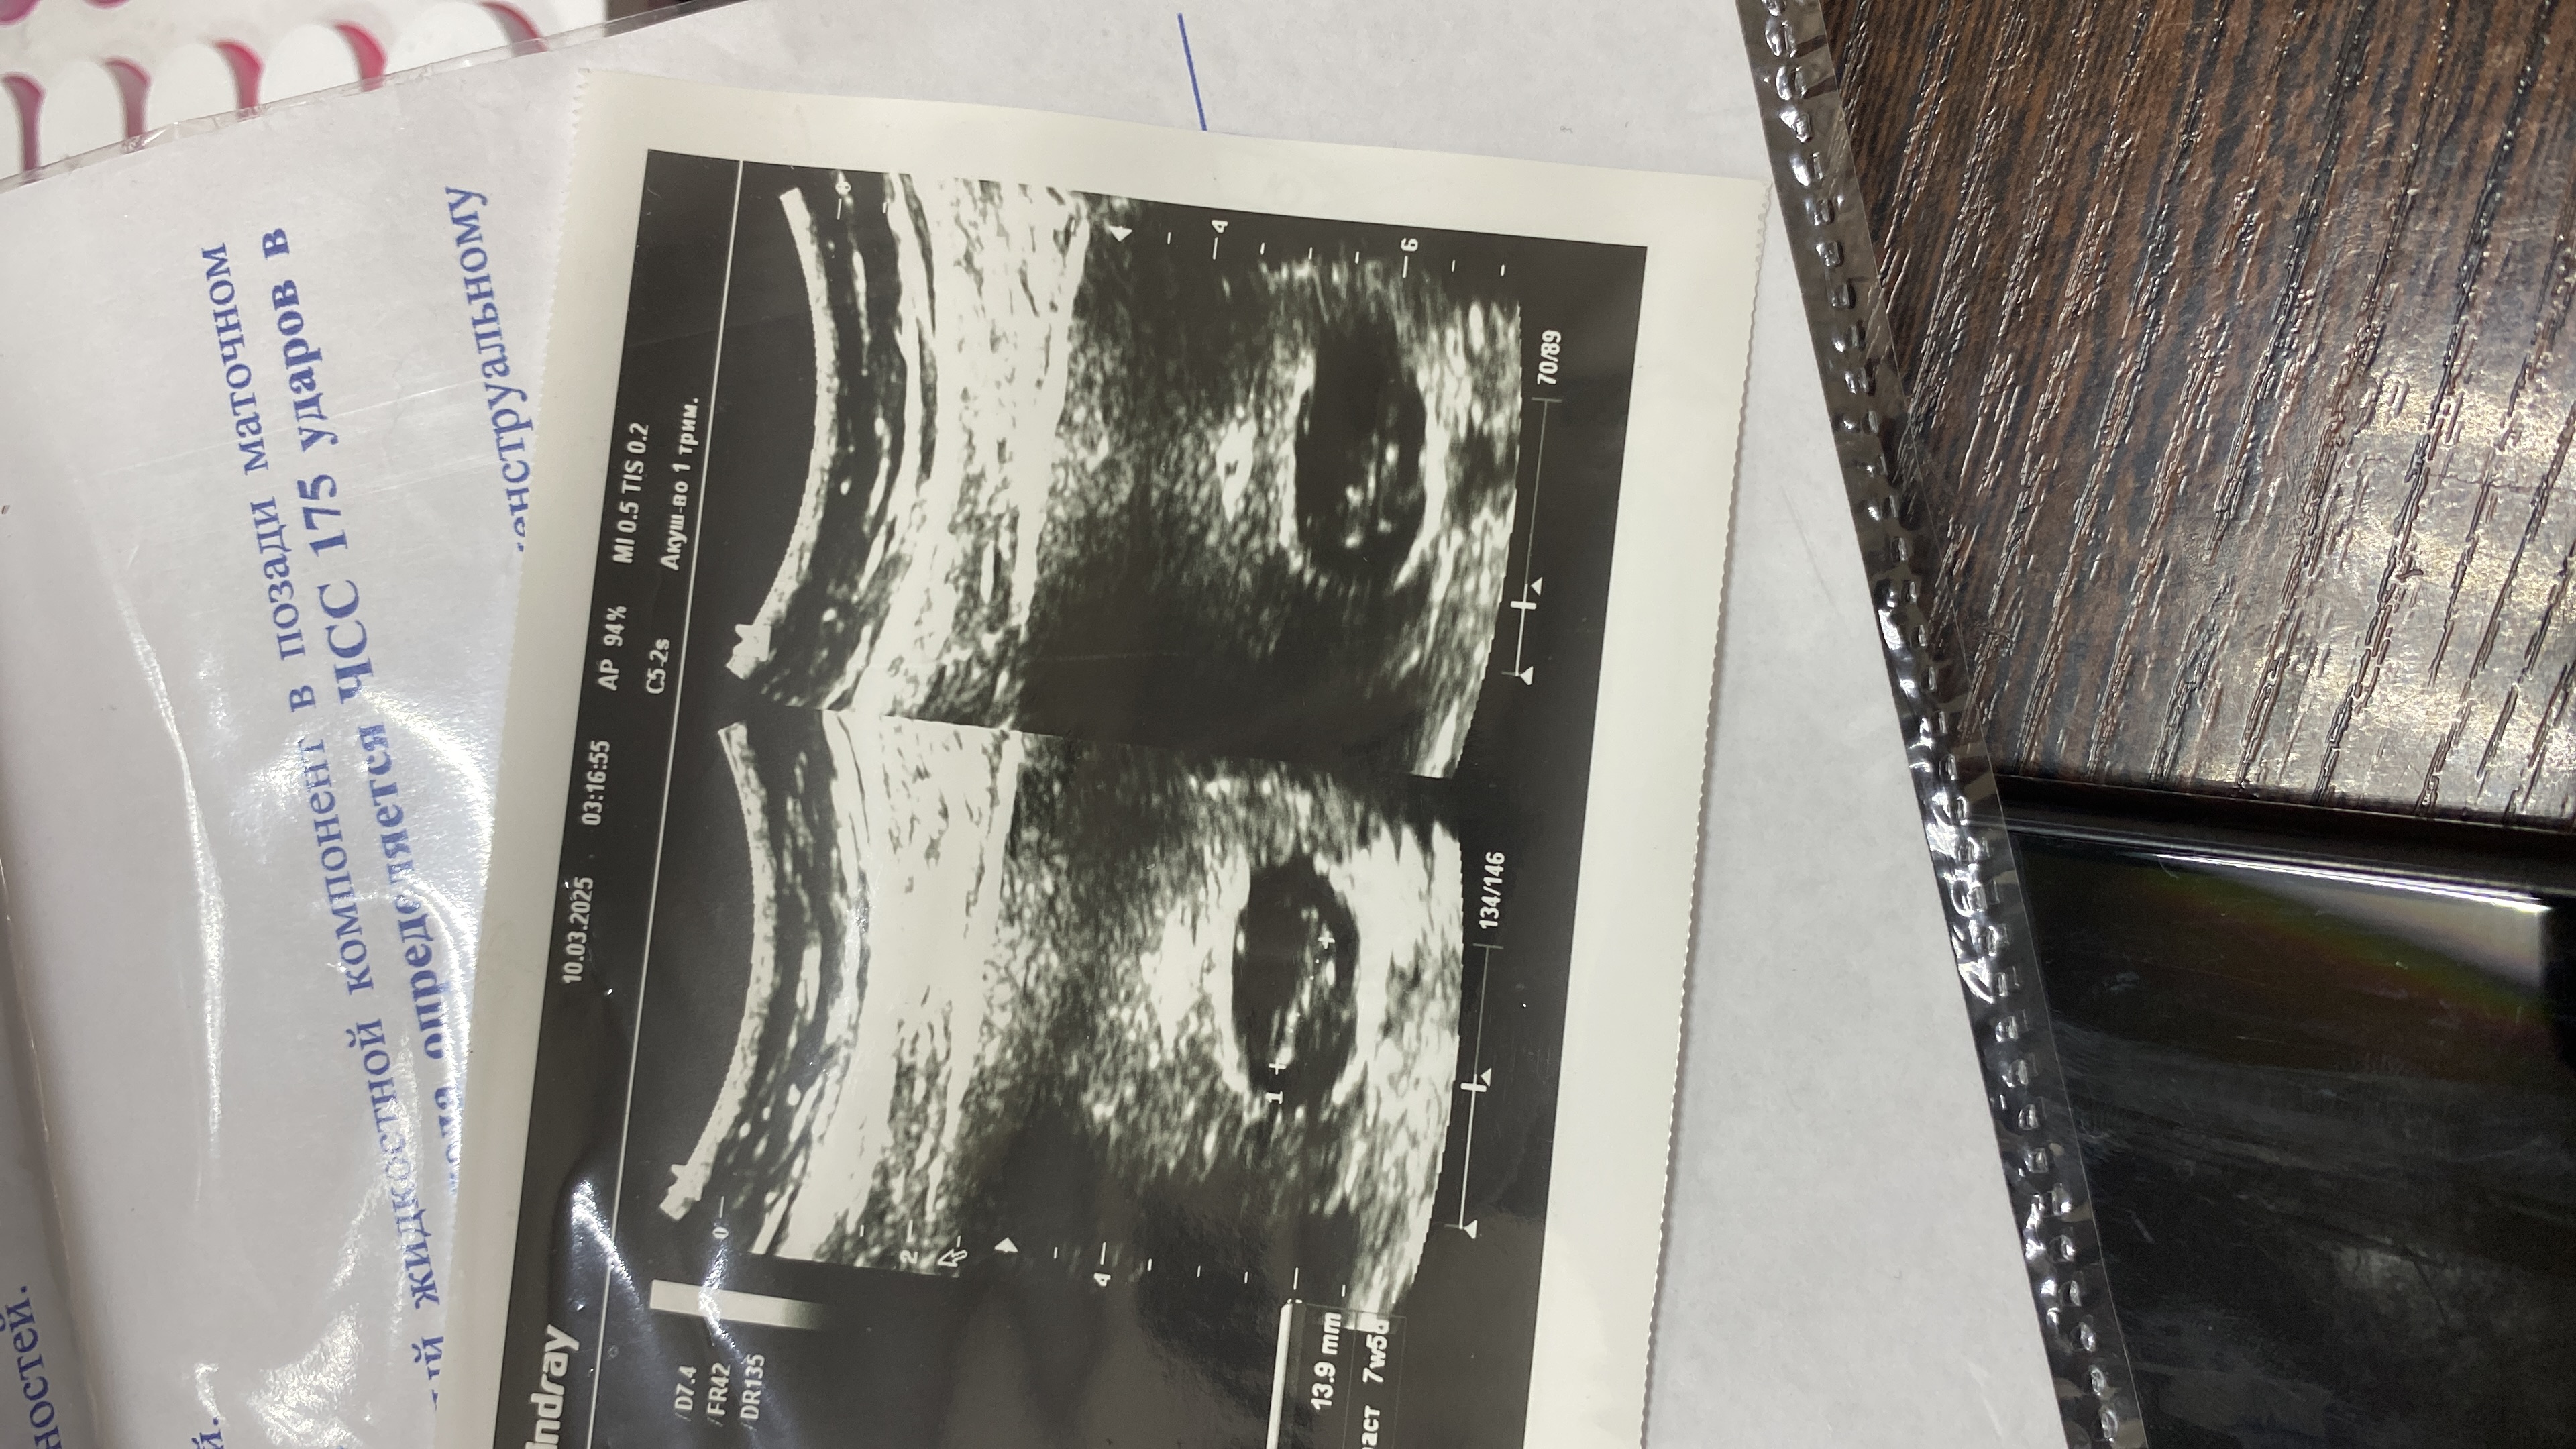

10.03.2025г Приехала на узи, услышала радостные новости эмбрион появился КТР 13,9мм, срок 7 недель и 5 дней, но плодное яйцо на 6-7 недель. В заключении узи «Признаки угрозы» А ещё очень большой желточный мешочек 9мм, что меня очень напугало, но узист сказал, что это не так страшно «высосет».

фото последнего узи